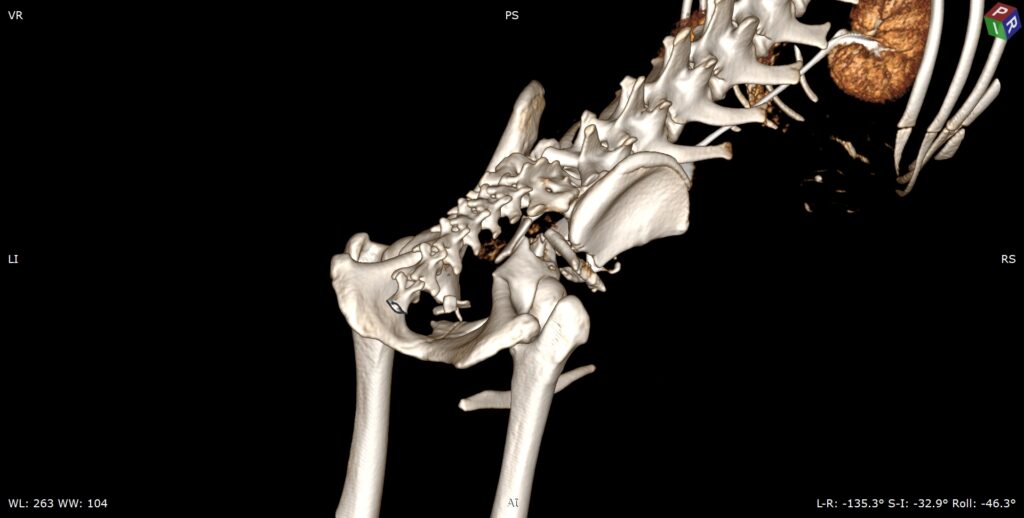

• En traumatologie, le scanner est devenu indispensable. Il permet d’évaluer avec précision l’étendue des lésions, le nombre et la taille des fragments osseux, l’atteinte des surfaces articulaires et les relations avec les tissus environnants. Ces informations conditionnent directement la stratégie chirurgicale et le pronostic fonctionnel.

Reconstruction tridimensionnelle d’une fracture du bassin complexe sur un Cocker.